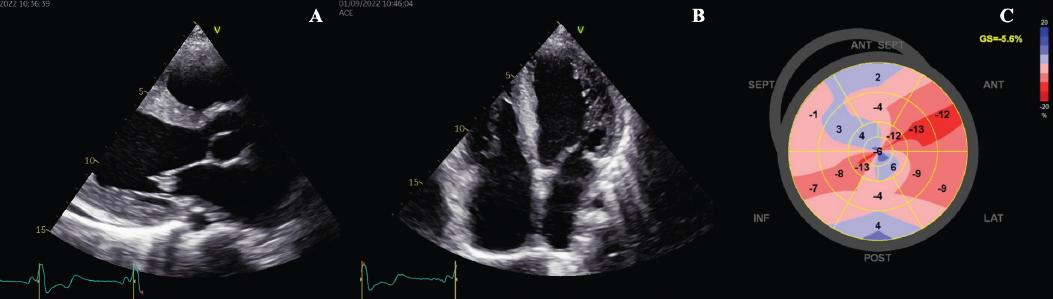

2D Echocardiography findings. A: Parasternal long axis with mild LVH (interventricular septum of 14 mm, posterior wall of 13mm). B: Apical 4 chamber view shows dilatation of all 4 chambers. C: Myocardial deformation bull’s eye showing severely reduced GLS of 05.6% with non-specific pattern.